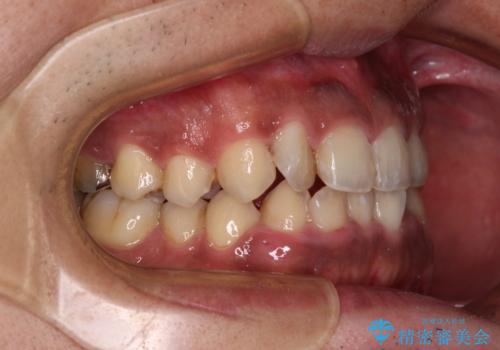

- 前歯のデコボコを気にして来院された患者様です。

前歯が90度近く捻れていたため、しっかりと治すことを考えるとワイヤー矯正の方がおすすめではありましたが、本人の希望によりインビザラインを用いて矯正治療を行うこととしました。

途中2年強の来院がなく、改善されていたデコボコが元に戻ったり、装着時間が不足しており前歯のデコボコは十分に改善することはできませんでしたが、5年間の有効期限内で可能な限り歯列を整えることができました。